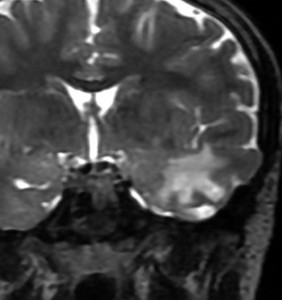

10才の時に,複雑部分発作(症候性てんかん)で発症しました。吐き気を感じた後に嘔吐して意識が遠くなる(意識減損)という症状であり,側頭葉てんかんです。脳波では左側頭葉に徐波律動がみられました。発作は頻回でしたがカルバマゼピンの投与で抑制されていましたが,MRIで腫瘍が発見されました。

左内側側頭葉グリオーマ mesial temporal glioma と呼ばれる腫瘍です。左の扁桃体,海馬鉤,海馬,海馬傍回に腫瘍が浸潤しています。T2強調画像とFLAIRでまだらな高信号で境界ははっきりしません。mass effectが少なく,増殖増大傾向のある腫瘍には見えないのが特徴です。下段右のように部分的にガドリニウム増強されるのも神経節細胞腫の特徴かもしれません。しかし,神経節膠腫,乏突起膠腫,乏突起星細胞腫(グレード2)なども疑われます。

手術中の脳波モニターでは,棘波が上側頭回の後方(ウェルニッケ領域)に存在し,深部電極刺入で海馬近傍にも棘波がみられましたが,もちろん上側頭回や海馬の切除はしませんでした。扁桃体 amygdala と海馬鈎 uncus の腫瘍部分のみを切除して手術を終了しています。海馬と海馬傍回には腫瘍を残しました。上のMRIは,その後6年経過した後のものですが腫瘍は全く同じ大きさです。抗てんかん薬も止めて,発作は全く生じていません。このような腫瘍は,扁桃体と海馬鉤を摘出することで,発作を完全に止めることができることがあります。ですから,最初の手術では,リスクのある余分な脳切除をしません。